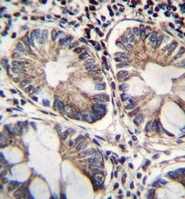

Supportive validation

- Submitted by

- OriGene (provider)

- Main image

- Experimental details

- Immunohistochemistry analysis in formalin fixed and paraffin embedded human rectum tissue reacted with NAD-ME?Antibody (C-term) ?, which was peroxidase conjugated to the secondary antibody and?followed by?DAB staining.

- Validation comment

- IHC